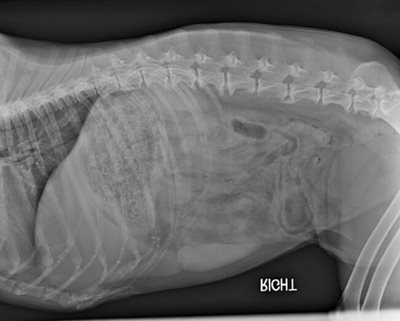

In September of 2019, Sammy presented with low energy, decreased appetite, on and off diarrhea, and shaking. There was a wide range of possible underlying issues. In order to determine what was going on with Sammy, her veterinarian performed blood work and x-rays, followed by an ultrasound examination.

Abdominal x-rays revealed fluid in the intestines, and the subsequent ultrasound showed fluid in the abdomen and enlarged abdominal lymph nodes. Slides were made of cells extracted from the lymph nodes, and were sent out to the external laboratory. These revealed reactive lymph nodes, caused by inflammation or cancer. Her blood work showed an increase in a liver enzyme called ALP, and a mild decrease in albumin.